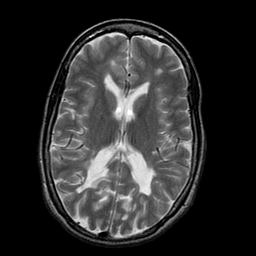

Multiple Sclerosis, MR Study mr-t2 -- Slice #12

[Home][Help][Clinical] Slice 12